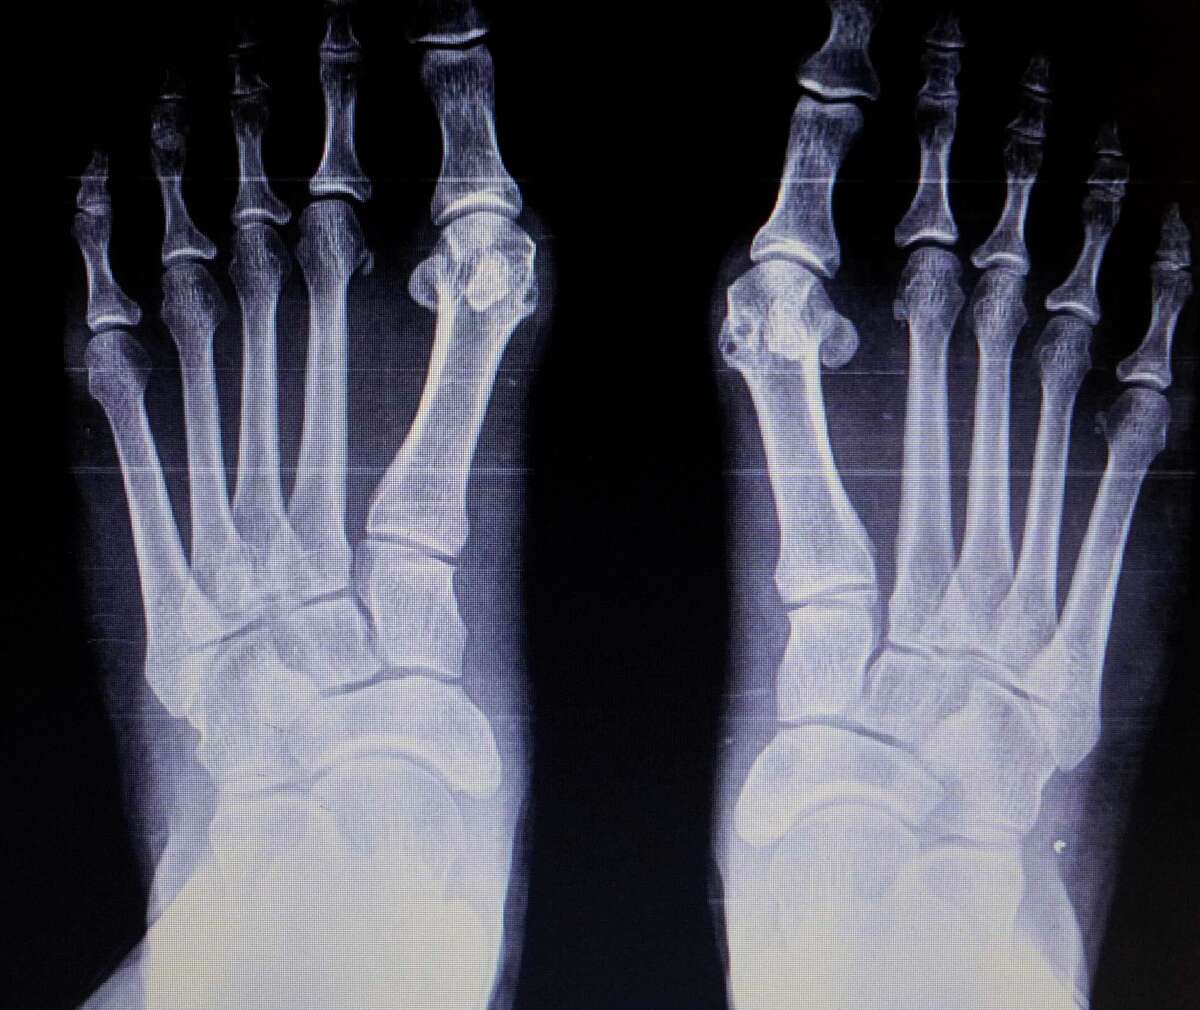

Bunion Correction Xray . Web removing the swollen tissue from around your big toe joint. After the procedure (right), the bump has been shaved, but the toe deformity remains and is. Check the alignment of your toes and. Generally, observation is enough to diagnose a bunion, as the bump is obvious on the side of the foot or base of the. Web hallux valgus, commonly referred to as a bunion, is a complex valgus deformity of the first ray that can cause. Straightening your big toe by removing part of the bone.

After the procedure (right), the bump has been shaved, but the toe deformity remains and is. Generally, observation is enough to diagnose a bunion, as the bump is obvious on the side of the foot or base of the. Web hallux valgus, commonly referred to as a bunion, is a complex valgus deformity of the first ray that can cause. Web removing the swollen tissue from around your big toe joint. Check the alignment of your toes and. Straightening your big toe by removing part of the bone.

Xrays after bunion surgery predict risk of recurrence Wimbledon Clinics Bunion Correction Xray Web hallux valgus, commonly referred to as a bunion, is a complex valgus deformity of the first ray that can cause. After the procedure (right), the bump has been shaved, but the toe deformity remains and is. Generally, observation is enough to diagnose a bunion, as the bump is obvious on the side of the foot or base of the.. Bunion Correction Xray.